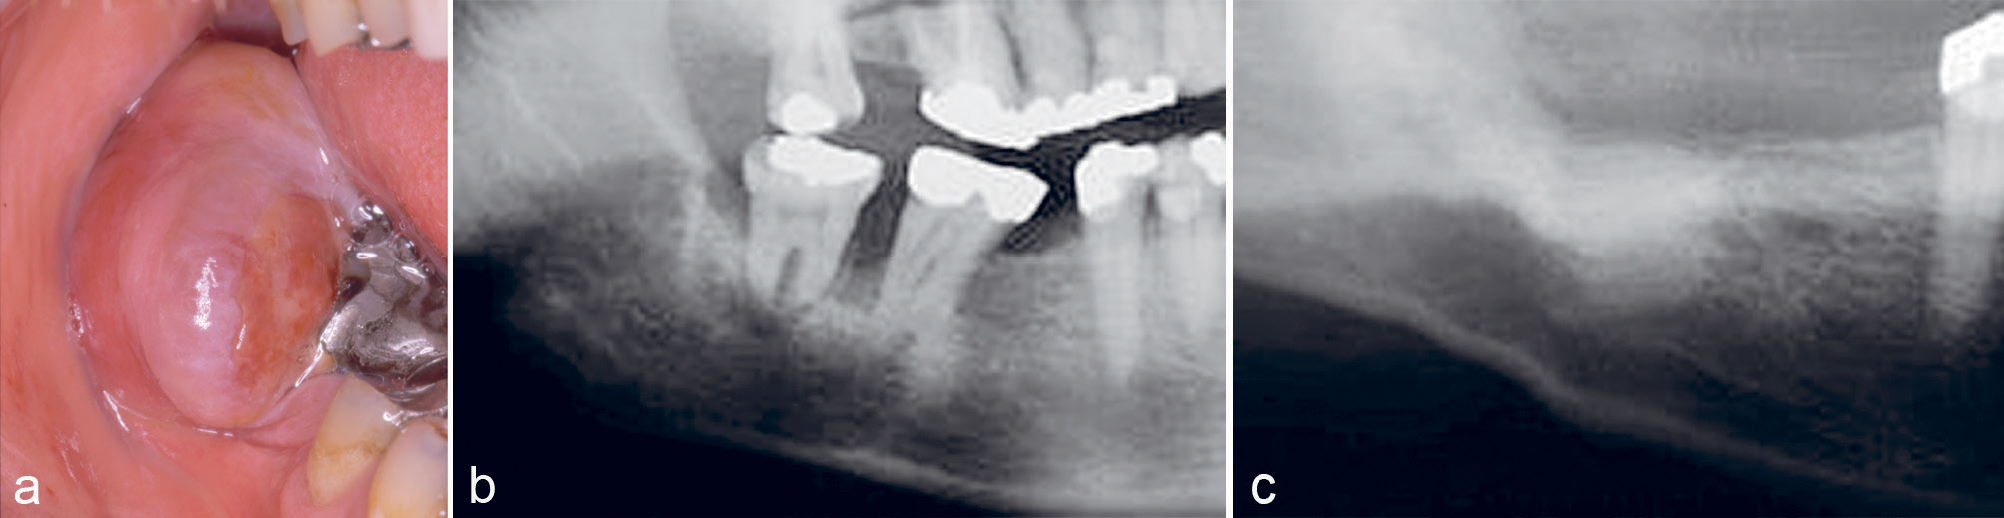

Kasus 10

En 45-årig mann var henvist fra egen tannlege for fjerning av tumor regio 47–48. Dette var et tilfeldig funn hos egen tannlege, pasienten hadde ingen subjektive symptomer. Undersøkelse viste en 30–40 mm stor tumor som vokste opp over occlusalplanet av 47 (figur 8a). Pasienten hadde en anamnese med testikkel-cancer, og av den grunn ble pyogent granulom eller metastase kliniske overveielser. Det histologiske bildet viste igjen PKCG. På grunn av hastehenvisning ble den delen av tumor som var inne i benet ikke fjernet (figur 8b). Det ble gjort to måneder senere, og diagnosen var den samme. Siden det meste av tumor lå utenfor ben, ble dette karakterisert som PKCG og ikke sentralt kjempecellegranulom. Seks måneder postoperativt var det full tilheling klinisk og røntgenologisk uten tegn til residiv (figur 8c).

Figur 8. Kasus 10. PKCG hos en 45-årig mann med nedbrytning av ben marginalt (a, b). Postoperativ kontroll 6 måneder etter fjerning av benet del av PKCG, uten tegn til residiv (c).